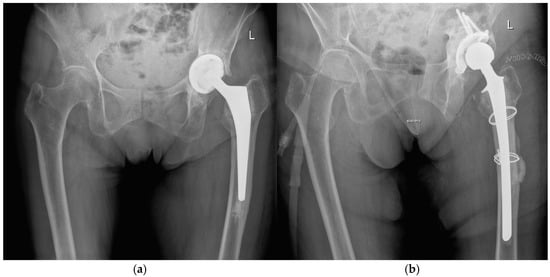

During the first-stage procedure, the infected implants were removed, and a cemented antibiotic-loaded spacer was implanted (104 times using an endofemoral approach and 182 times using a transfemoral approach) (Figure 1). The local antibiotic admixture was selected according to the antibiogram, as described previously [2,6]. The most frequently used antibiotics were gentamicin, clindamycin, and vancomycin, which were consistently applied in combination to optimize local bioavailability and improve elution characteristics. Radical debridement was performed, and a local antiseptic solution was applied. Additional intraoperative samples for microbiology and histology were obtained. Postoperatively, patients received a standardized antibiotic regimen consisting of 2 weeks of intravenous therapy followed by 4 weeks of oral antibiotics according to the antibiogram of the microorganisms.

Figure 1.

Radiographs of a two-stage procedure using a transfemoral approach performed on a 87-year-old women: (a) infected prosthesis with loosening of the cup and cemented stem; (b) temporary implanted spacer with cemented cup and cemented stem using a transfemoral approach; (c) reimplanted cementless prosthesis using the transfemoral approach; (d) one year follow-up of the reimplanted prosthesis with osseointegration of the components into the bone.

At the time of reimplantation, the spacer was removed, followed by thorough debridement, application of a local antiseptic solution, and reimplantation of a new prosthesis (Figure 1). Again, patients received 2 weeks of intravenous antibiotics followed by 4 weeks of oral therapy, according to the susceptibility of microorganisms.